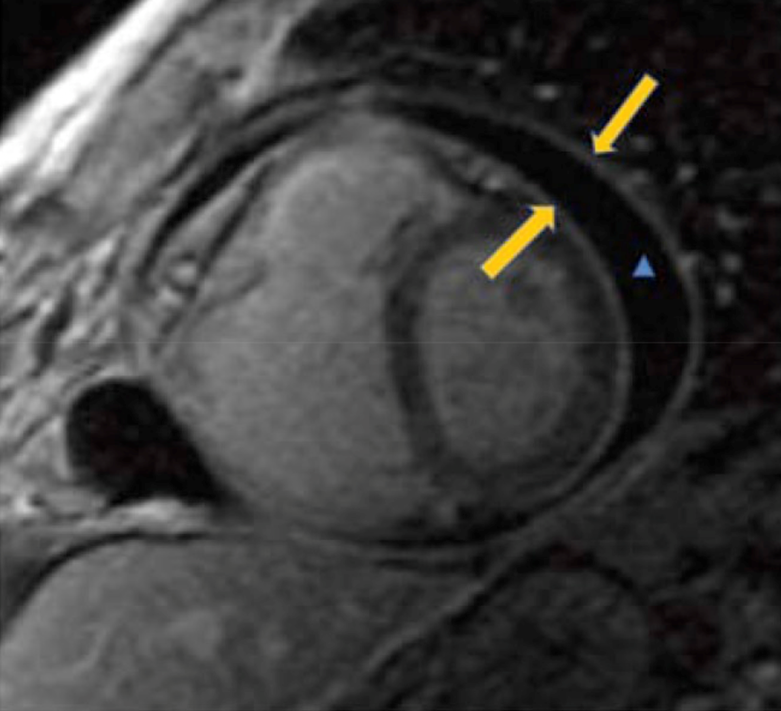

МРТ сердца с контрастированием обладает высокой чувствительностью в идентификации стадии воспаления и определения фазы заболевания. Позднее накопление препаратов гадолиния (АТХ V08CA Парамагнитные контрастные средства) при магнитно-резонансной томографии сердца с контрастированием обладает 94% чувствительностью в определении степени воспалительного поражения перикарда (рисунок 4) [33].

Рисунок 4. Позднее накопление препаратов гадолиния (АТХ V08CA Парамагнитные контрастные средства) при магнитно-резонансной томографии сердца с контрастированием. Незначительное утолщение париетального и висцерального листков перикарда (желтые стрелки) и перикардиальный выпот между ними (синяя стрелка) [33].